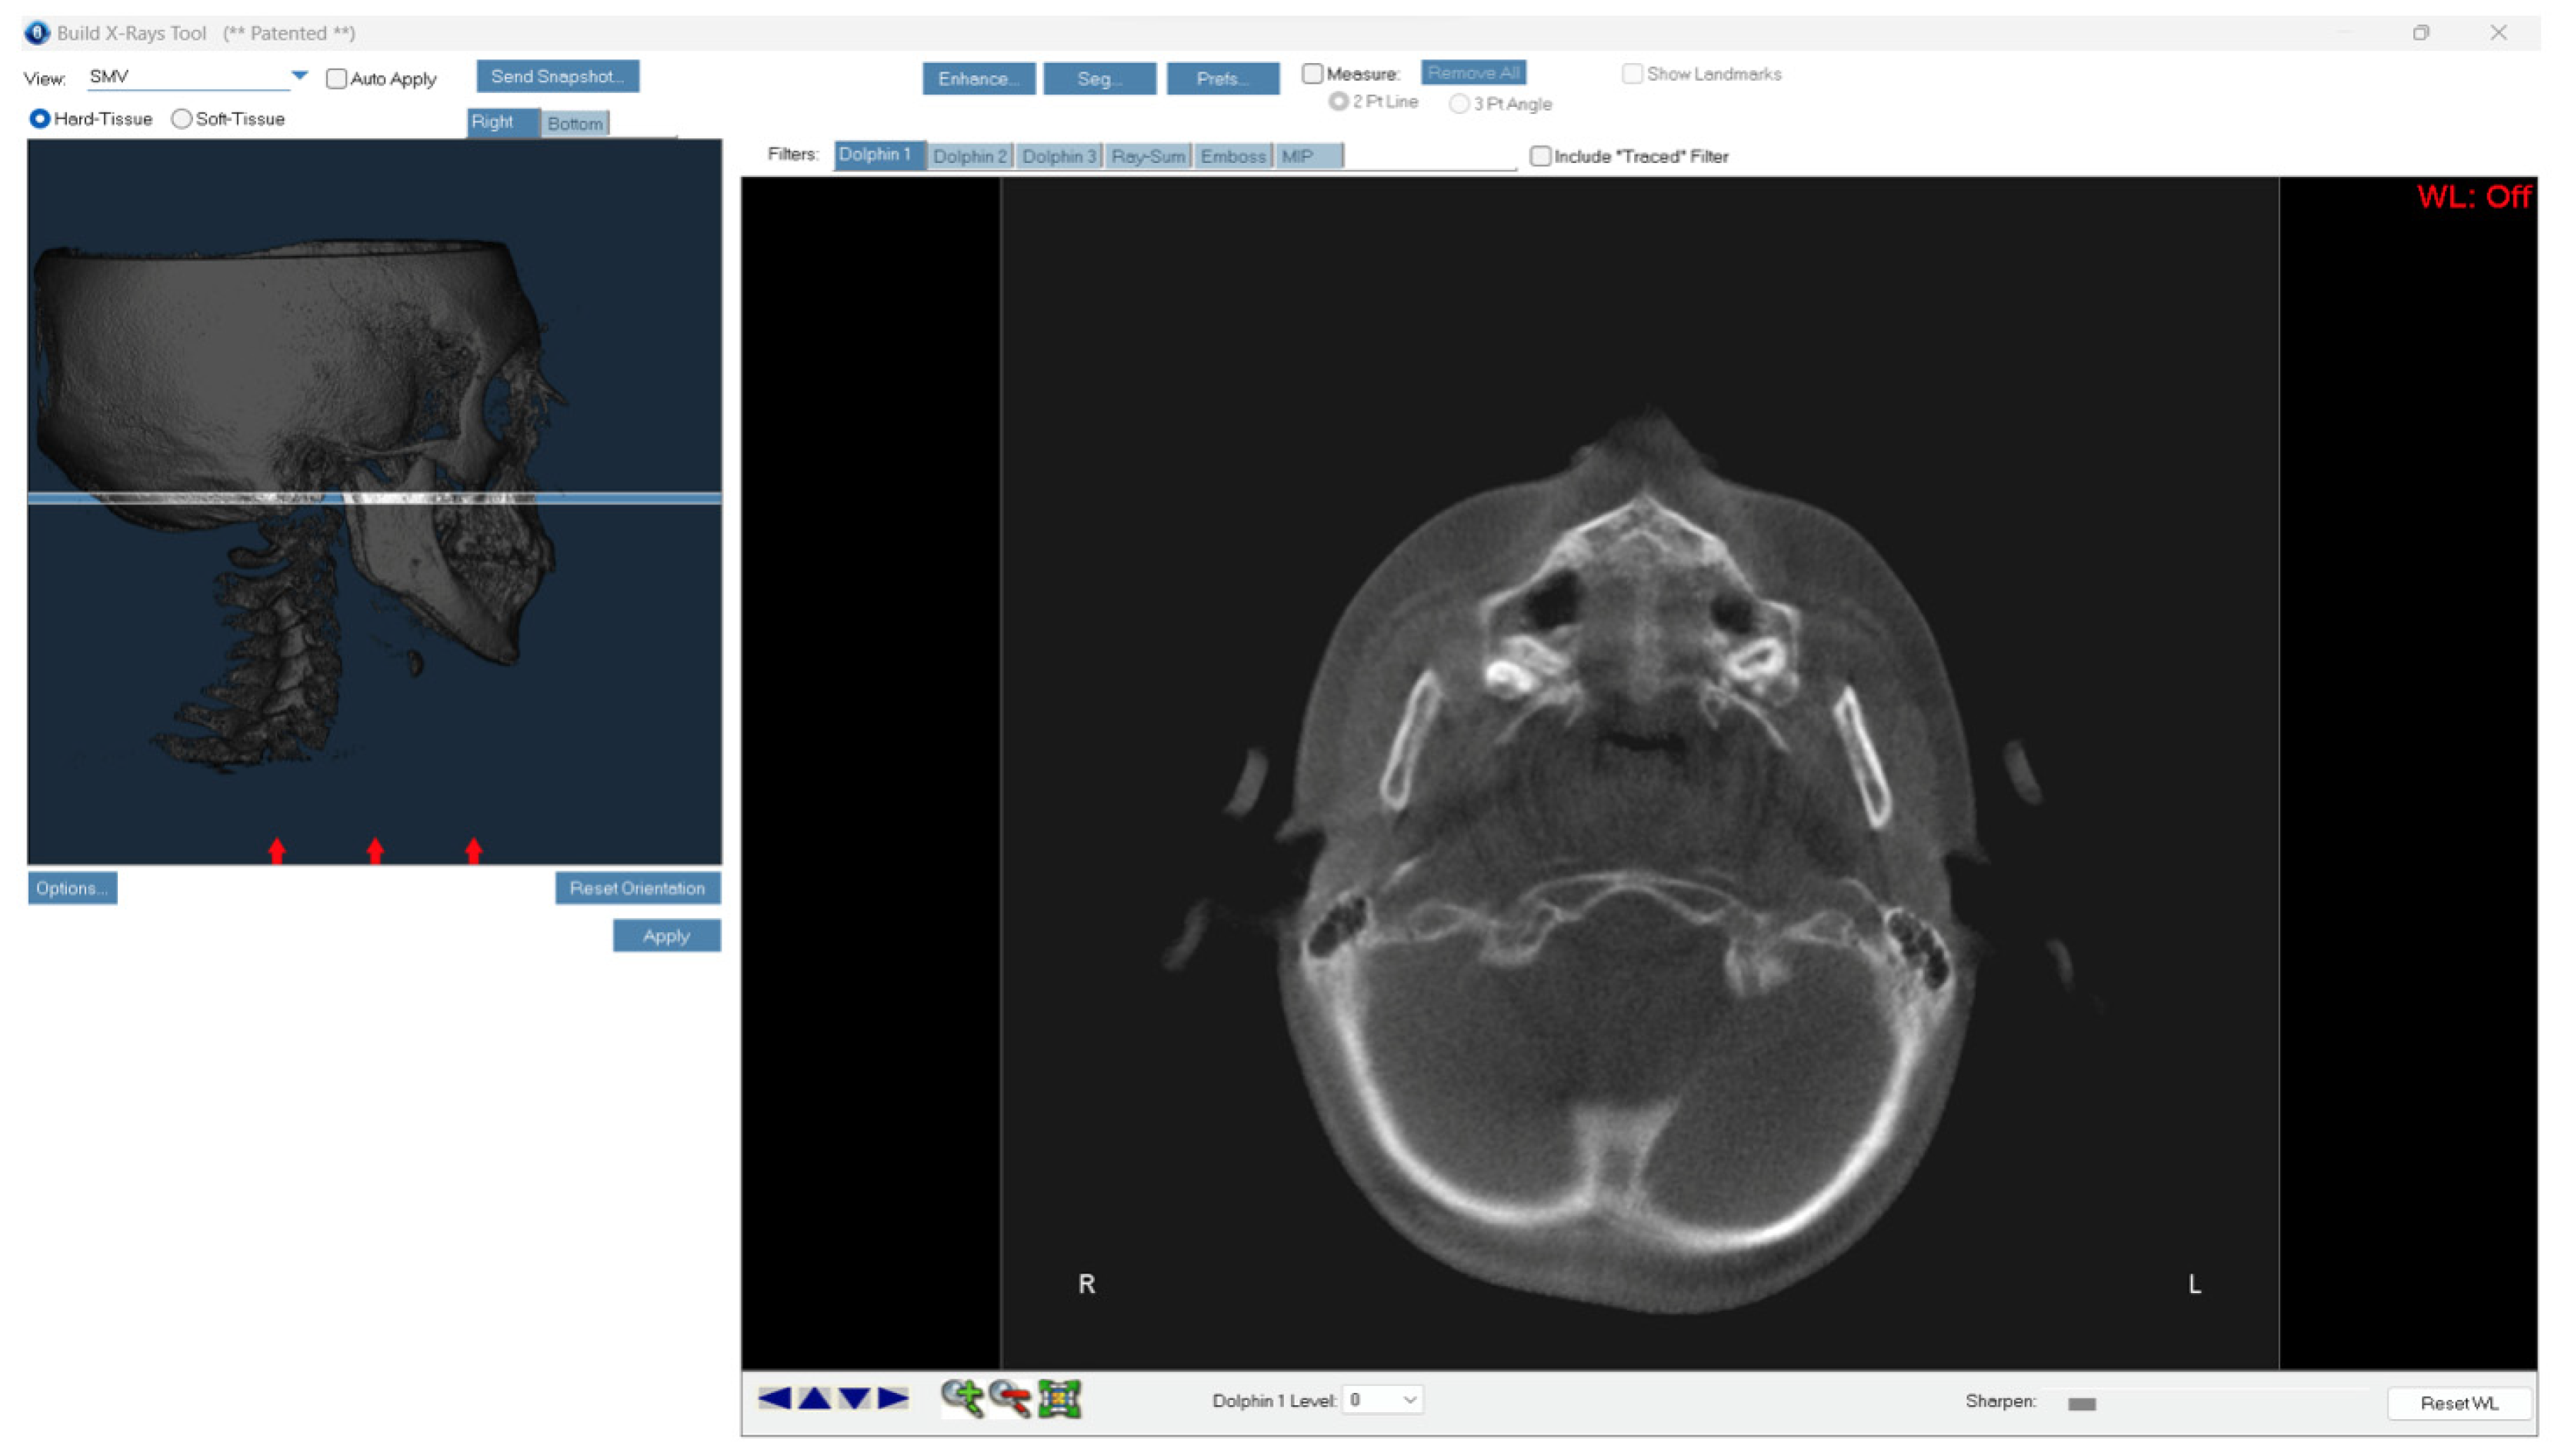

- Stage A refers to a relatively straight high-density line at the midline with no or little interdigitations;

- Stage B shows a scalloped high-density line at the midline with an irregular shape;

- Stage C presents two parallel, scalloped, high-density lines close to each other and separated in some areas by small low-density spaces;

- Stage D indicates a complete fusion in the palatine bone, where the midpalatal suture cannot be visualised;